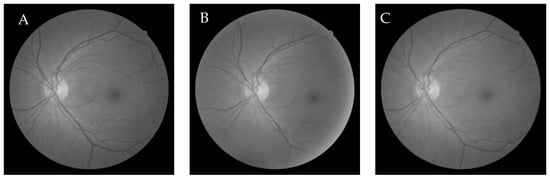

6.2.4. Genetic Algorithm-Based Wang’s Demons Registration